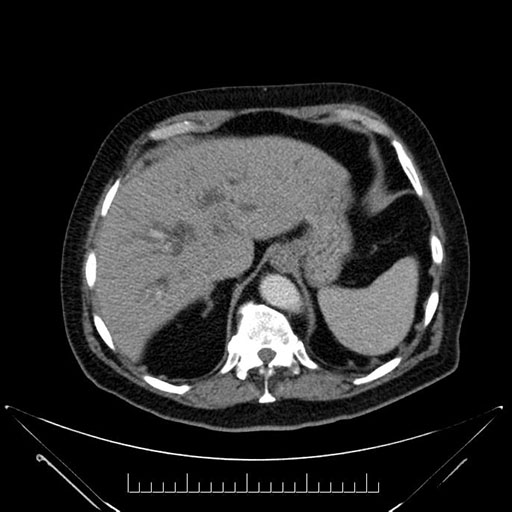

Axial - 3 months prior